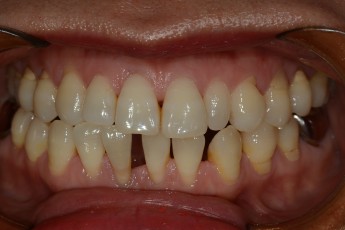

BEFORE & AFTER

- 덧니교정